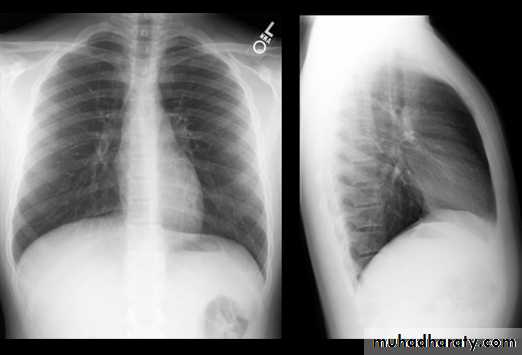

Normal chest XR PA & lateral view

Look carefully on both diaphragmatic cruse costo & cardio phrenic angles

8.normal chest XR PA & lat. view

9.normal radiologic anatomy of the chest

10.normal chest anatomy